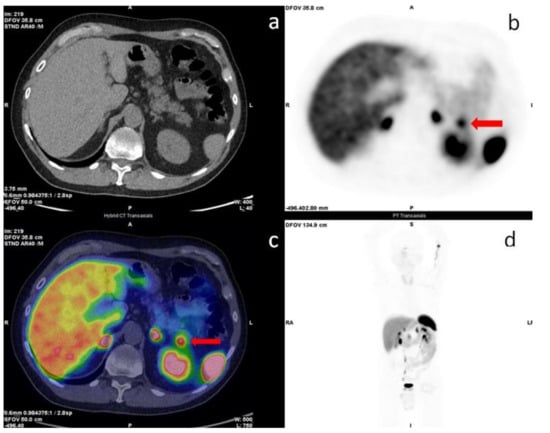

- Cuthbertson, D.J.; Banks, M.; Khoo, B.; Antwi, K.; Christ, E.; Campbell, F.; Raraty, M.; Wild, D. Application of Ga(68)-DOTA-exendin-4 PET/CT to localize an occult insulinoma. Clin. Endocrinol. 2016, 84, 789–791. [Google Scholar] [CrossRef]

- Bongetti, E.; Lee, M.H.; Pattison, D.A.; Hicks, R.J.; Norris, R.; Sachithanandan, N.; MacIsaac, R.J. Diagnostic challenges in a patient with an occult insulinoma: 68 Ga-DOTA-exendin-4 PET/CT and 68Ga-DOTATATE PET/CT. Clin. Case Rep. 2018, 6, 719–722. [Google Scholar] [CrossRef]